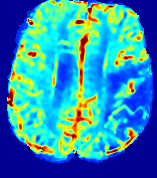

LesionRefer to captionRefer to captionRefer to captionRefer to captionRefer to captionRefer to caption𝐕rgbsubscript𝐕𝑟𝑔𝑏{\bf{V}}_{rgb}Refer to captionRefer to captionRefer to captionRefer to captionRefer to captionRefer to caption𝐕2subscriptnorm𝐕2{\|\bf{V}}\|_{2}Refer to captionRefer to captionRefer to captionRefer to captionRefer to captionRefer to captionRefer to caption3.53.53.52.82.82.82.12.12.11.41.41.40.70.70.70.00.00.0(mm/s)𝑚𝑚𝑠(mm/s)D𝐷DRefer to captionRefer to captionRefer to captionRefer to captionRefer to captionRefer to captionRefer to caption0.0200.0200.0200.0160.0160.0160.0120.0120.0120.0080.0080.0080.0040.0040.0040.0000.0000.000(mm2/s)𝑚superscript𝑚2𝑠(mm^{2}/s)Slice #1Slice #2Slice #3Slice #4Slice #5Slice #6

Figure 3: PIANO feature maps for one stroke patient, where the lesion is located in the left hemisphere. Top row: segmented stroke lesion region (white) on different slices, obtained from ISLES 2017. The corresponding slices for the PIANO feature maps are shown in the following rows.

For a better insight into an estimated velocity field 𝐕𝐕{\bf{V}} and diffusion field 𝐃𝐃{\bf{D}}, we compute the following maps: (1) 𝐕rgbsubscript𝐕𝑟𝑔𝑏{\bf{V}}_{rgb}: Color-coded orientation map of 𝐕=(Vx,Vy,Vz)T𝐕superscriptsuperscript𝑉𝑥superscript𝑉𝑦superscript𝑉𝑧𝑇{\bf{V}}=(V^{x},V^{y},V^{z})^{T}, obtained by normalizing 𝐕𝐕{\bf{V}} to unit length and mapping its 3 components to red, green, blue respectively; (2) 𝐕2subscriptnorm𝐕2\|{\bf{V}}\|_{2}: 222 norm of 𝐕𝐕{\bf{V}}; (3) D𝐷D: scalar field in Eq. 5.

Fig. 3 and Fig. 4 show the PIANO feature maps estimated from two ISLES 2017 patients: all are highly consistent with the lesion in both cases. Details of the blood flow trajectories are revealed in 𝐕rgbsubscript𝐕𝑟𝑔𝑏{\bf{V}}_{rgb} by the ridged patterns and the sharp changes of colors in the unaffected (right) hemisphere, while the flat patterns appearing within the lesion provide little directional information about the velocity and indicate low velocity magnitudes. Velocity magnitudes are more directly visualized via 𝐕2subscriptnorm𝐕2\|{\bf{V}}\|_{2}, from which one can easily locate the lesion where 𝐕2subscriptnorm𝐕2\|{\bf{V}}\|_{2} is low. D𝐷D also indicates lower diffusion values in the lesion, though with less contrast potentially due to the fact that it captures the accumulated effect of CA diffusion at the voxel-level.